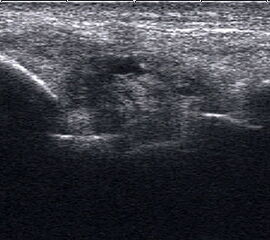

Fibulaverletzung beim Kind

Abgehobenes Periost mit periostalem Hämatom (rechts) mit Gegenseite (links). Die Kortikalis wird unterbrochen von der noch offenen Wachstumsfuge der Fibula.

Abbildung 12

Lagerung: Rückenlage, leichte Innrotation des Fußes.

Schnittebene: LS über distaler Fibula.

Referenzstruktur: Fibula im Längsverlauf.

Befunde: Bei Kindern wird nach Distorsion des OSG mitunter eine Lösung der Fibulafuge vermutet, die jedoch in der klinischen Praxis sehr selten ist. Die seitenvergleichende Untersuchung zeigt dann ein aufgrund des dicken und bei Kindern gut abgrenzbaren echogenen Periosts ein periostales Hämatom, was aber auch ein Hinweis auf eine Fissur oder Fraktur sein kann (Abb.12).